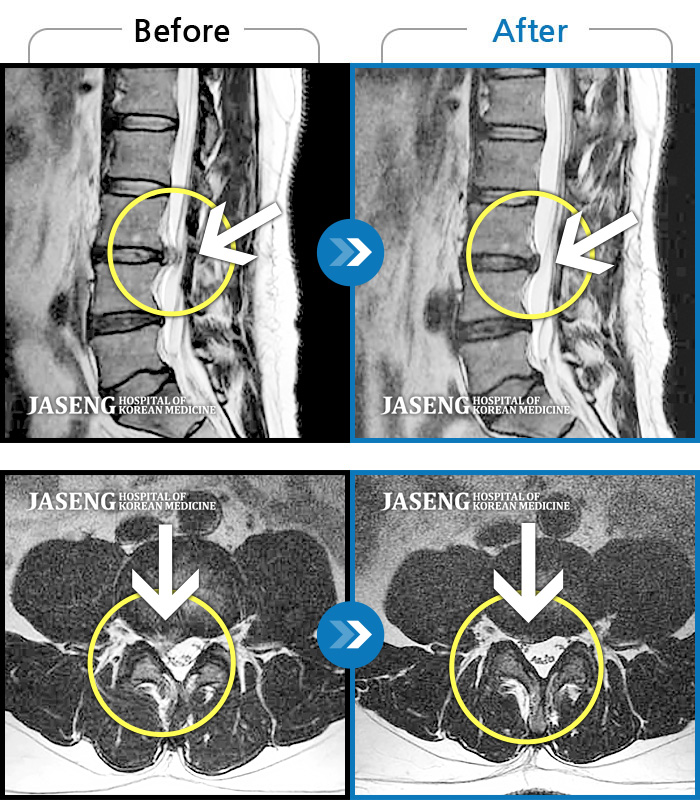

허리디스크

잠실 · 한상욱 원장

우측 엉치부터 우측 다리부터 발끝까지 저리고 아프다. 감각까지 먹먹하다.

촬영시기

2022.04.15 ~ 2022.10.22

2022.12.02